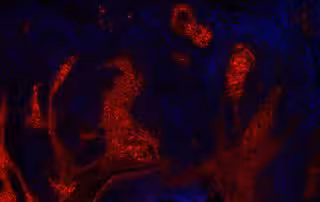

Carcinoma de células escamosas de la piel que expresa el mensajero angiopoyetina-like 4 (ANGPLT4).

Carcinoma de células escamosas de la piel que expresa el mensajero angiopoyetina-like 4 (ANGPLT4). - AUGUSTIN/DKFZ

Esta investigación, publicada en la revista científica 'Journal of Experimental Medicine', ha estudiado ahora con más detalle el mensajero angiopoyetina 4 (ANGPLT4).